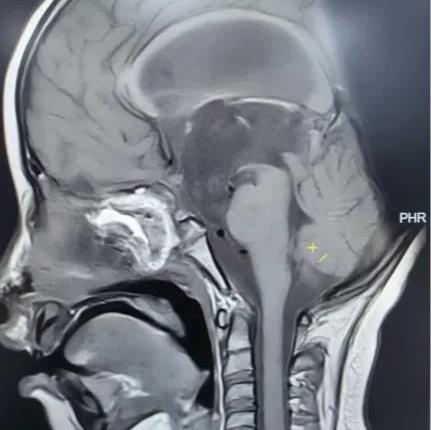

术后垂体MRI增强检查

手术中,团队借助高清4K神经内镜,凭借精湛的显微操作技术,细致分离肿瘤与周围神经、血管的粘连。历经3小时,肿瘤被完整切除,下丘脑、垂体柄、视神经等重要结构均得到完好保护。术后病理确诊为颅咽管瘤。

在医护团队的精心照护下,欢欢神经功能障碍明显改善,视力逐渐恢复,头痛症状完全消失,梗阻性脑积水得到有效缓解。之后顺利拔除脑室引流管,未出现脑脊液漏、感染等并发症,内分泌功能也通过药物获得精准调控。